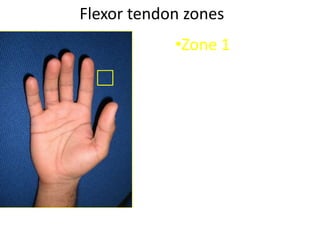

- It describes flexor tendon zones, extensor compartments, and pulley system anatomy.